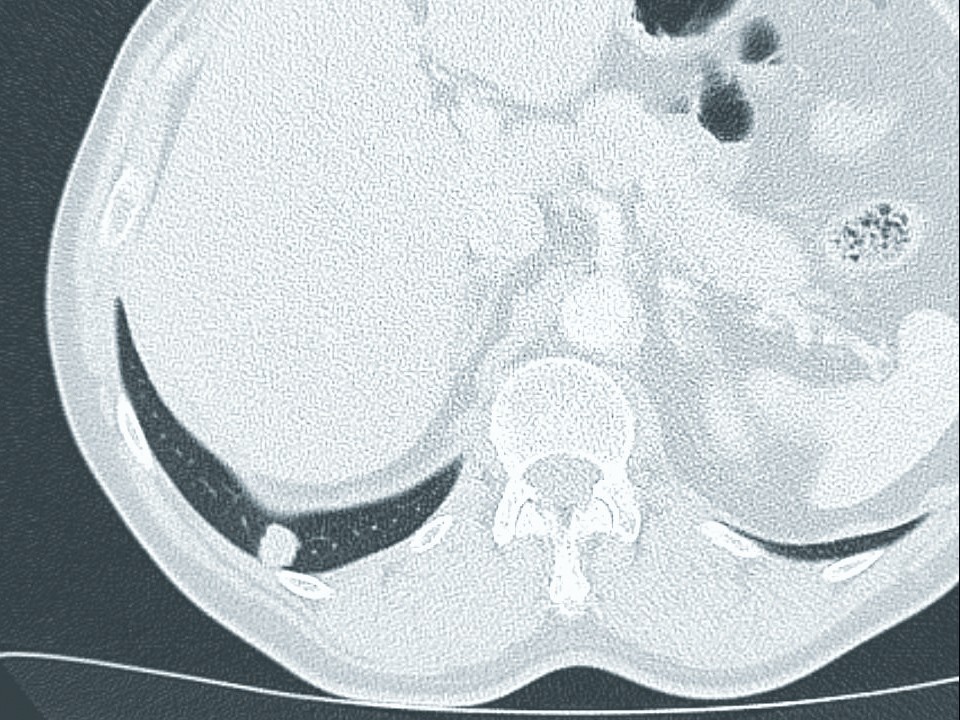

In der radiologischen Praxis wird – nach Überprüfung des Berichtes und der Teilnahmevoraussetzungen (z. B. kein Thorax-CT in den vergangenen 12 Monaten) – ein Untersuchungstermin zur Niedrigdosis-CT vergeben. Genaue Vorgaben für die Durchführung der Niedrigdosis-CT sind in der Lungenkrebs- Früherkennungs-Verordnung beschrieben [18]. So darf ein Volumen-Computertomographie-Dosisindex von 1,3 Milligray nicht oder nur im Einzelfall aufgrund der Körperstatur (z. B. bei Adipositas) überschritten werden. In der Verordnung zwingend vorgeschrieben ist die Verwendung von Software zur computerassistierten Detektion zur Unterstützung des Radiologen. Nach Beurteilung der CT-Bilder und Überprüfung auf Auffälligkeiten in einer ersten Sitzung durch den Erstbefunder erfolgt durch diesen eine zweite, durch die Software unterstützte Befundung (Rundherderkennung, Volumenbestimmung, Volumenverdoppelungszeit etc.). Sollten sich auffällige Befunde ergeben, werden diese durch einen zweiten Radiologen (Zweitbefunder, in einem Lungenzentrum) begutachtet.

Hieraus ergibt sich eine gemeinsame abschließende Beurteilung. Die radiologische Auswertung erfolgt als strukturierte Befundung gemäß der sogenannten modifizierten Lung-RADS-Klassifikation mit Volumenverdopplungszeit [23]. Das weitere Vorgehen hängt vom Ergebnis ab, wobei es drei Kategorien gibt. Bei einem unauffälligen Befund wird nach 12 Monaten eine erneute Niedrigdosis-CT durchgeführt. Bei einem kontrollbedürftigen Befund (= mutmaßlich gutartig oder nicht verdächtig genug, um eine invasive Abklärung zu rechtfertigen) sollen z. B. vorzeitige Kontrollen mittels Niedrigdosis-CT nach drei oder sechs Monaten durchgeführt werden. Bei einem abklärungsbedürftigen Befund (= sehr verdächtiger Befund) soll eine zeitnahe klinische Abklärung erfolgen (Besprechung in Fallkonferenz, invasive Diagnostik (Biopsie)).